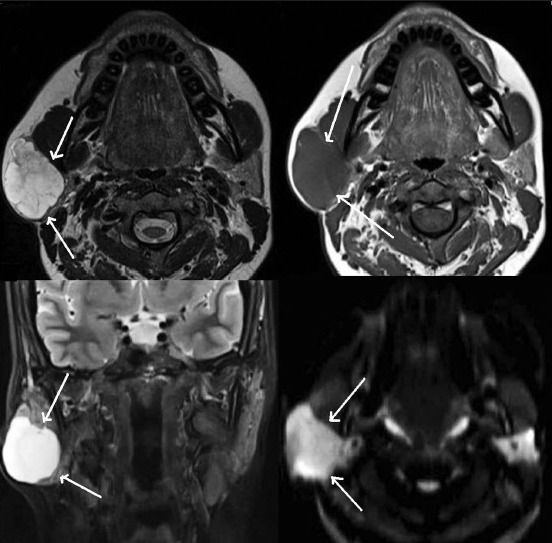

(Слева) На аксиальной КТ шеи с КУ определяется односторонняя аплазия поднижнечелюстной железы. Левая поднижнечелюстная железа отсутствует, правая поднижнечелюстная железа в целом не изменена, хотя и немного увеличена. Левая ямка содержит жир, мелкие лимфоузлы и лицевую вену.

(Справа) На корональной КТ с КУ у этого же пациента определяется аплазия левой поднижнечелюстной железы и легкое увеличение правой поднижнечелюстной железы.

(Слева) На аксиальной КТ с КУ отсутствует правая поднижнечелюстная железа. Левая поднижнечелюстная железа слегка гипертрофирована.

(Справа) На аксиальной КТ с КУ определяется жировая атрофия левой поднижнечелюстной железы, обусловленная закупоркой вартонова протока сиалолитом, который не визуализируется на этом срезе. Вартонов проток может присутствовать даже при аплазии железы.